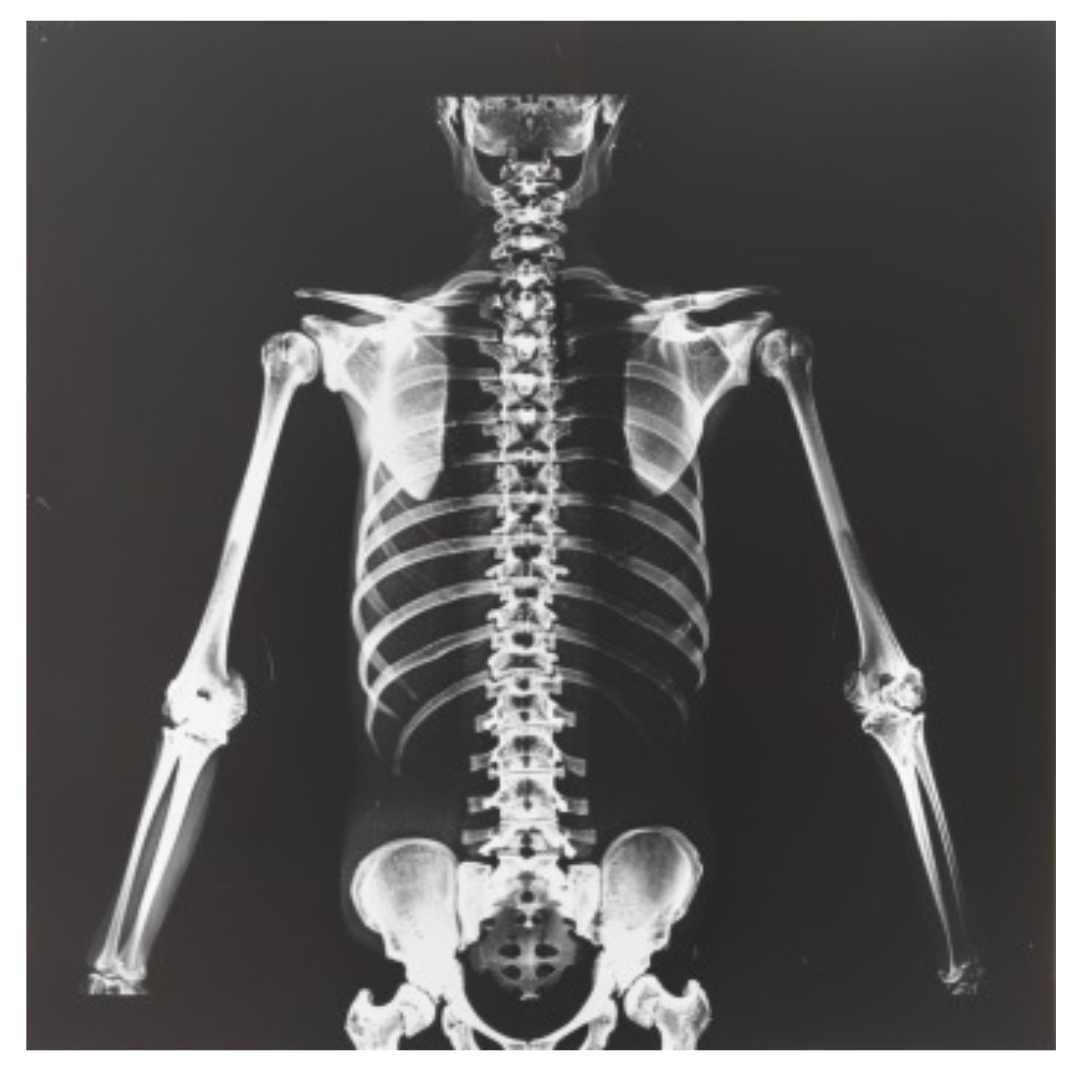

1. 어깨통증 원인 - 회전근개 파열 (Rotator Cuff Tear)

회전근개는 어깨 관절을 감싸고 있는 근육과 힘줄의 집합체입니다. 이 회전근개가 파열되면 어깨 통증이 굉장히 심해질 수 있습니다.

파열이 크면 어깨를 들어 올리는 것조차 힘들어지고, 작은 움직임에도 극심한 통증이 느껴질 수 있어요.

회전근개 파열은 보통 과도한 사용이나 노화로 인해 발생하는 경우가 많습니다. 어깨를 자주 쓰는 운동선수나, 반복적인 작업을 하는 사람들에게 많이 나타나죠.